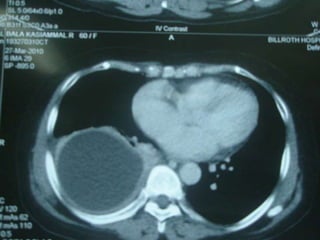

a.2. Tomodensitométrie thoracique

• Pas indispensable au diagnostic de kyste

hydatique du poumon

• Utile dans le bilan lésionnel pré opératoire.

• Analyse paroi du kyste, topographie, rapports

avec bronches et structures vasculaires.

KH à localisation hépatique et   KHP fissuré aspect serpigineux de

pulmonaire                       la membrane proligère